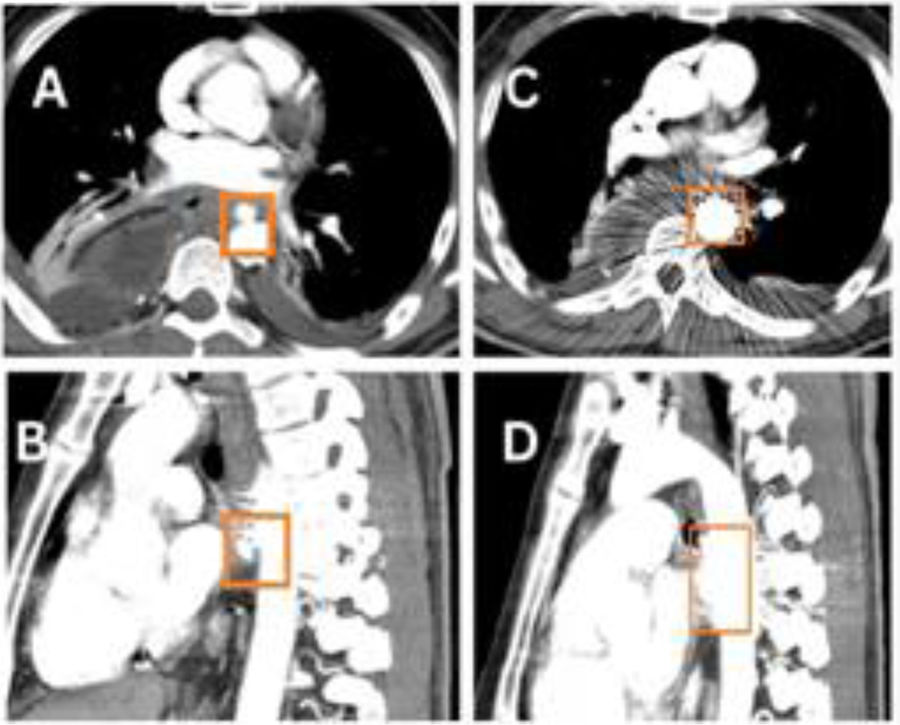

Vista axial (A) y sagital (B) del aortograma con TC posterior a la primera colocación de stent en la aorta, mostrando la cobertura parcial de la comunicación fistulosa. Vista axial (C) y sagital (D) del aortograma con TC posterior a la segunda colocación del stent en la aorta, mostrando la cobertura total de la comunicación fistulosa.